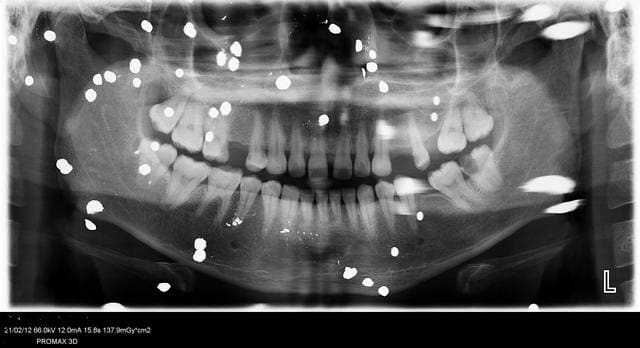

Tout est là , merci de vos avis éclairés .

reprendre une rétro, sans le matériaux d'obturation sur le capteur ou sur l'étuis du capteur, ça fait une tache a l'apex.

Je ne comprend pas ou le probleme, c'est quoi qui vous empeche de faire une restauration classique sur cette dent?

J'ai loupé quelque chose ?

Si douleurs, extraction direct. Je te trouve deja bien assez genereux, ambitieux, inconscient, audacieux...

Sinon, compo et dans 6 mois-1 an un bel inlay, si il n'y a aucune image radio (auquel cas retour 1ere option).